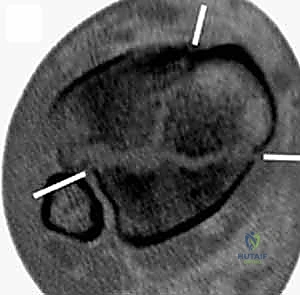

2. التصوير المقطعي المحوسب (CT Scan) - المعيار الذهبي

لا يمكن إجراء جراحة حديثة لكسر البيلون دون إجراء أشعة مقطعية. لماذا؟

كشفت الأبحاث المتقدمة (مثل أبحاث كول Cole وزملائه) والتي يعتمد عليها الدكتور هطيف، أن الأشعة المقطعية، وخاصة مع إعادة البناء ثلاثي الأبعاد (3D Reconstruction)، تسمح برسم خريطة دقيقة لكل قطعة عظمية مفتتة في السطح المفصلي (AO/OTA 43-C3).

تظهر الأشعة المقطعية النمط الثابت لتفتت البيلون والذي يتكون عادة من ثلاث قطع رئيسية:

* القطعة الأمامية الجانبية (Chaput fragment): متصلة بالرباط الظنبوبي الشظوي الأمامي.

* القطعة الخلفية (Volkmann fragment): متصلة بالرباط الظنبوبي الشظوي الخلفي.

* القطعة الأنسية (Medial Malleolus): متصلة بالرباط الدالي.

وفي الوسط، توجد منطقة "الانهيار المفصلي" (Die-punch fragment) التي تُدفع داخل العظم.

يستخدم الأستاذ الدكتور محمد هطيف هذه الخريطة المقطعية لتحديد مسار الشقوق الجراحية، واختيار أحجام وأنواع الشرائح المعدنية المطلوبة، وتحديد تسلسل إرجاع القطع العظمية قبل دخول غرفة العمليات.